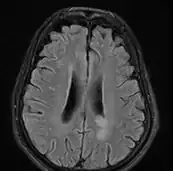

MRI brain: cryptococcus

Cryptococcal meningitis (infection of the meninges, the tissue covering the brain) is believed to result from dissemination of the fungus from either an observed or unappreciated pulmonary infection. Often there is also silent dissemination throughout the brain when meningitis is present. Cryptococcus gattii causes infections in immunocompetent people (fully functioning immune system), but C. neoformans v. grubii, and v. neoformans usually only cause clinically evident infections in persons with some form of defect in their immune systems (immunocompromised persons). People with defects in their cell-mediated immunity, for example, people with AIDS, are especially susceptible to disseminated cryptococcosis. Cryptococcosis is often fatal, even if treated.[19]